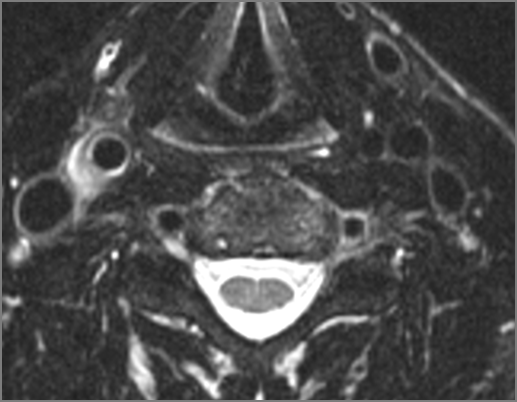

There is edema/abscess within in the prevertebral or paravertebral spaces. |

No | NA |

There is edema/abscess within in the epidural space. |

There is erosive process involving the disc spaces or other components of the spine. |